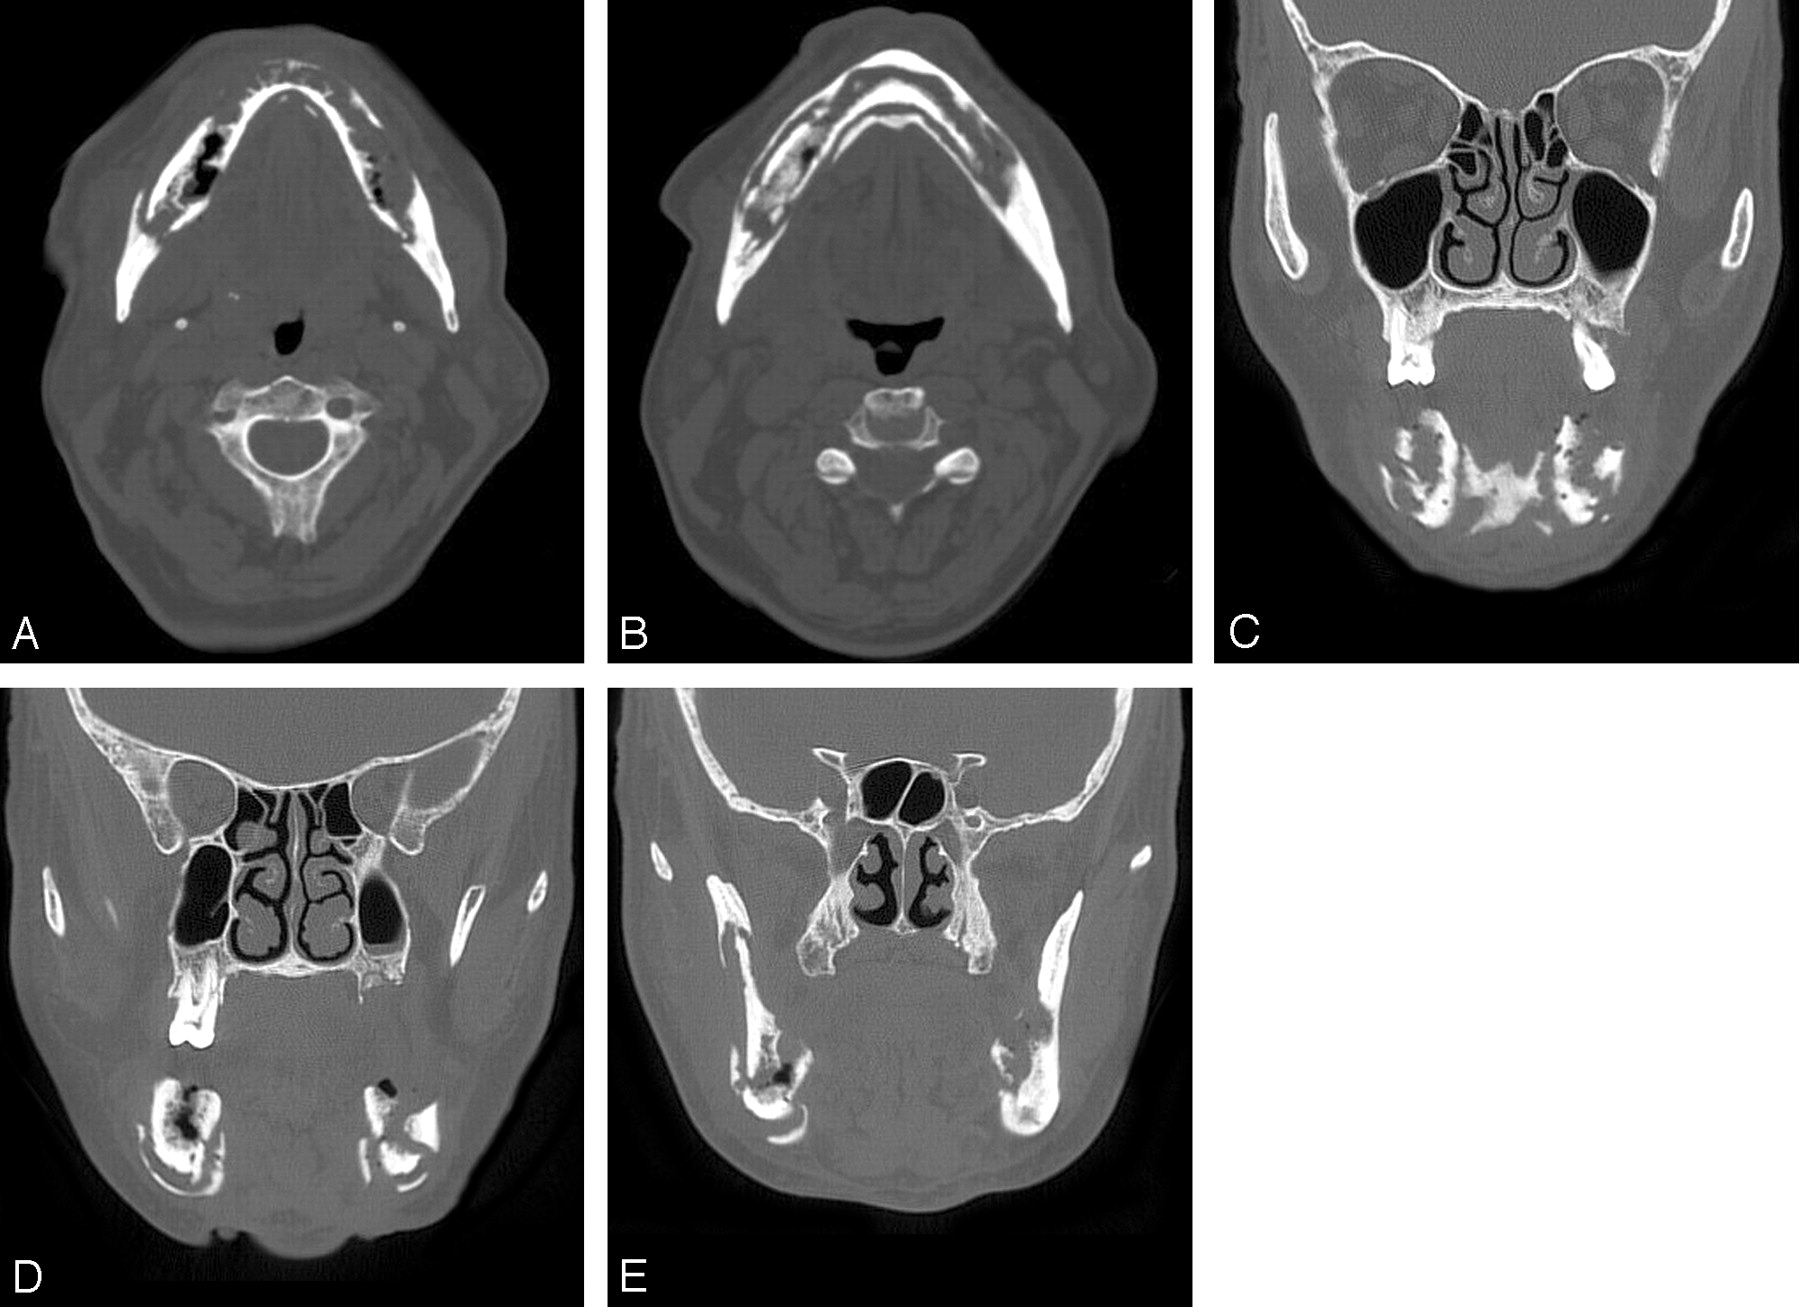

How Is ONJ Diagnosed?

Although there’s no specific diagnostic test for determining risk, osteonecrosis of the jaw is diagnosed by the presence of an exposed jaw bone that has persisted for eight weeks or more. You may have no visible sores in your mouth, but your dentist can determine if you have ONJ. When treated at this early stage, there’s a very good prognosis.